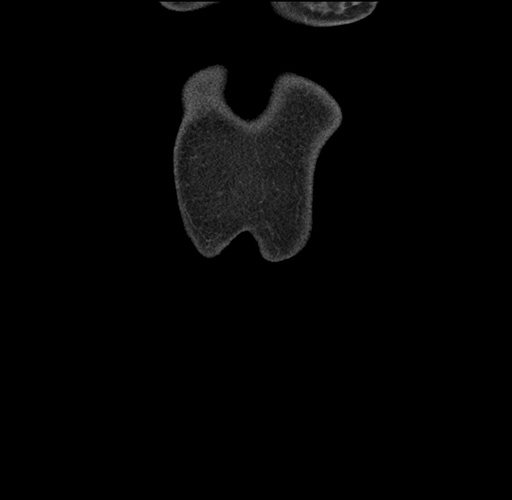

Imaging Analysis

Look through the patient's CT scan to identify any areas of concern for the necessary procedure.

Based on your CT findings, which issue(s) would give reason for "planned slowing down moment(s)" in this case?

Considering a standard left lateral sectionectomy procedure, what step(s) of the operation would you do differently in this case ?